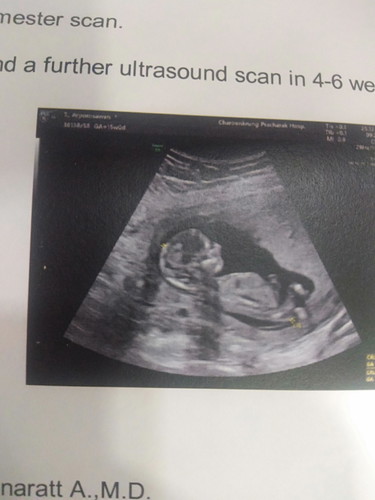

อัลตร้าซาวด์

เมื่อวานไปหาหมอมาคะ ได้อัลตร้าซาวด์แล้วเห็นลูกน้อย รู้สึกตื่นเต้นมากคะ หมอบอกว่าต้องดิ้นแต่แม่ยังไม่รู้สึกนะคะ สักพักน้องดิ้นหนีหมอเลยคะ อีแม่ก็รู้สึกตั้งแต่ 13 w แล้วคะ เพราะรู้สึกว่าปลาตอดบ่อยมาก ตอนนี้ 14 w คะ น้องดิ้นเก่งมาก